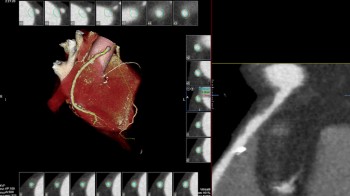

Također u slučaju pojave boli u prsima, gdje nema EKG promjena i lab.nalazi su uredni, radi se takozvani «triple rule-out» CT koronarografija-da bi se jednim pregledom isključila bolest koronarnih arterija, plućna tromboembolija ili disekcija aneurizme aorte, od kojih je svaka ponaosob potencijalno fatalna.

• MSCT koronarografija (prikaz krvnih žila srca CT-om, bez neugodnosti i komplikacija koje nosi klasična koronarografija), u saradnji s Poliklinkom dr.Al-Tawil